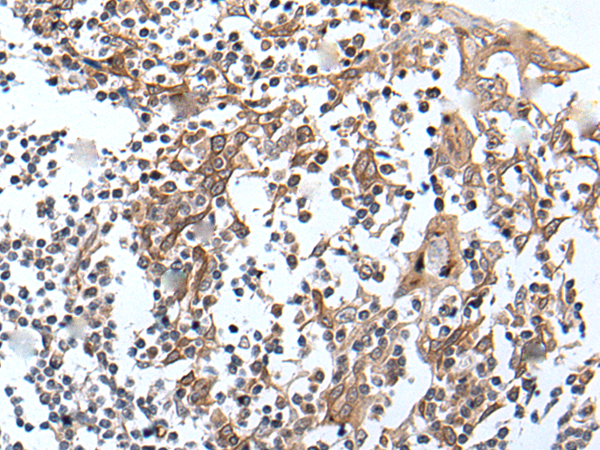

IHC positive control: |

Human ovarian cancer and human tonsil |